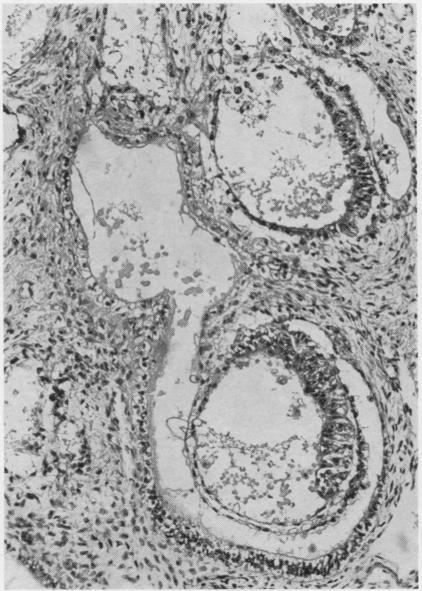

Developmental stages of embryo-like bodies in teratoma testis.